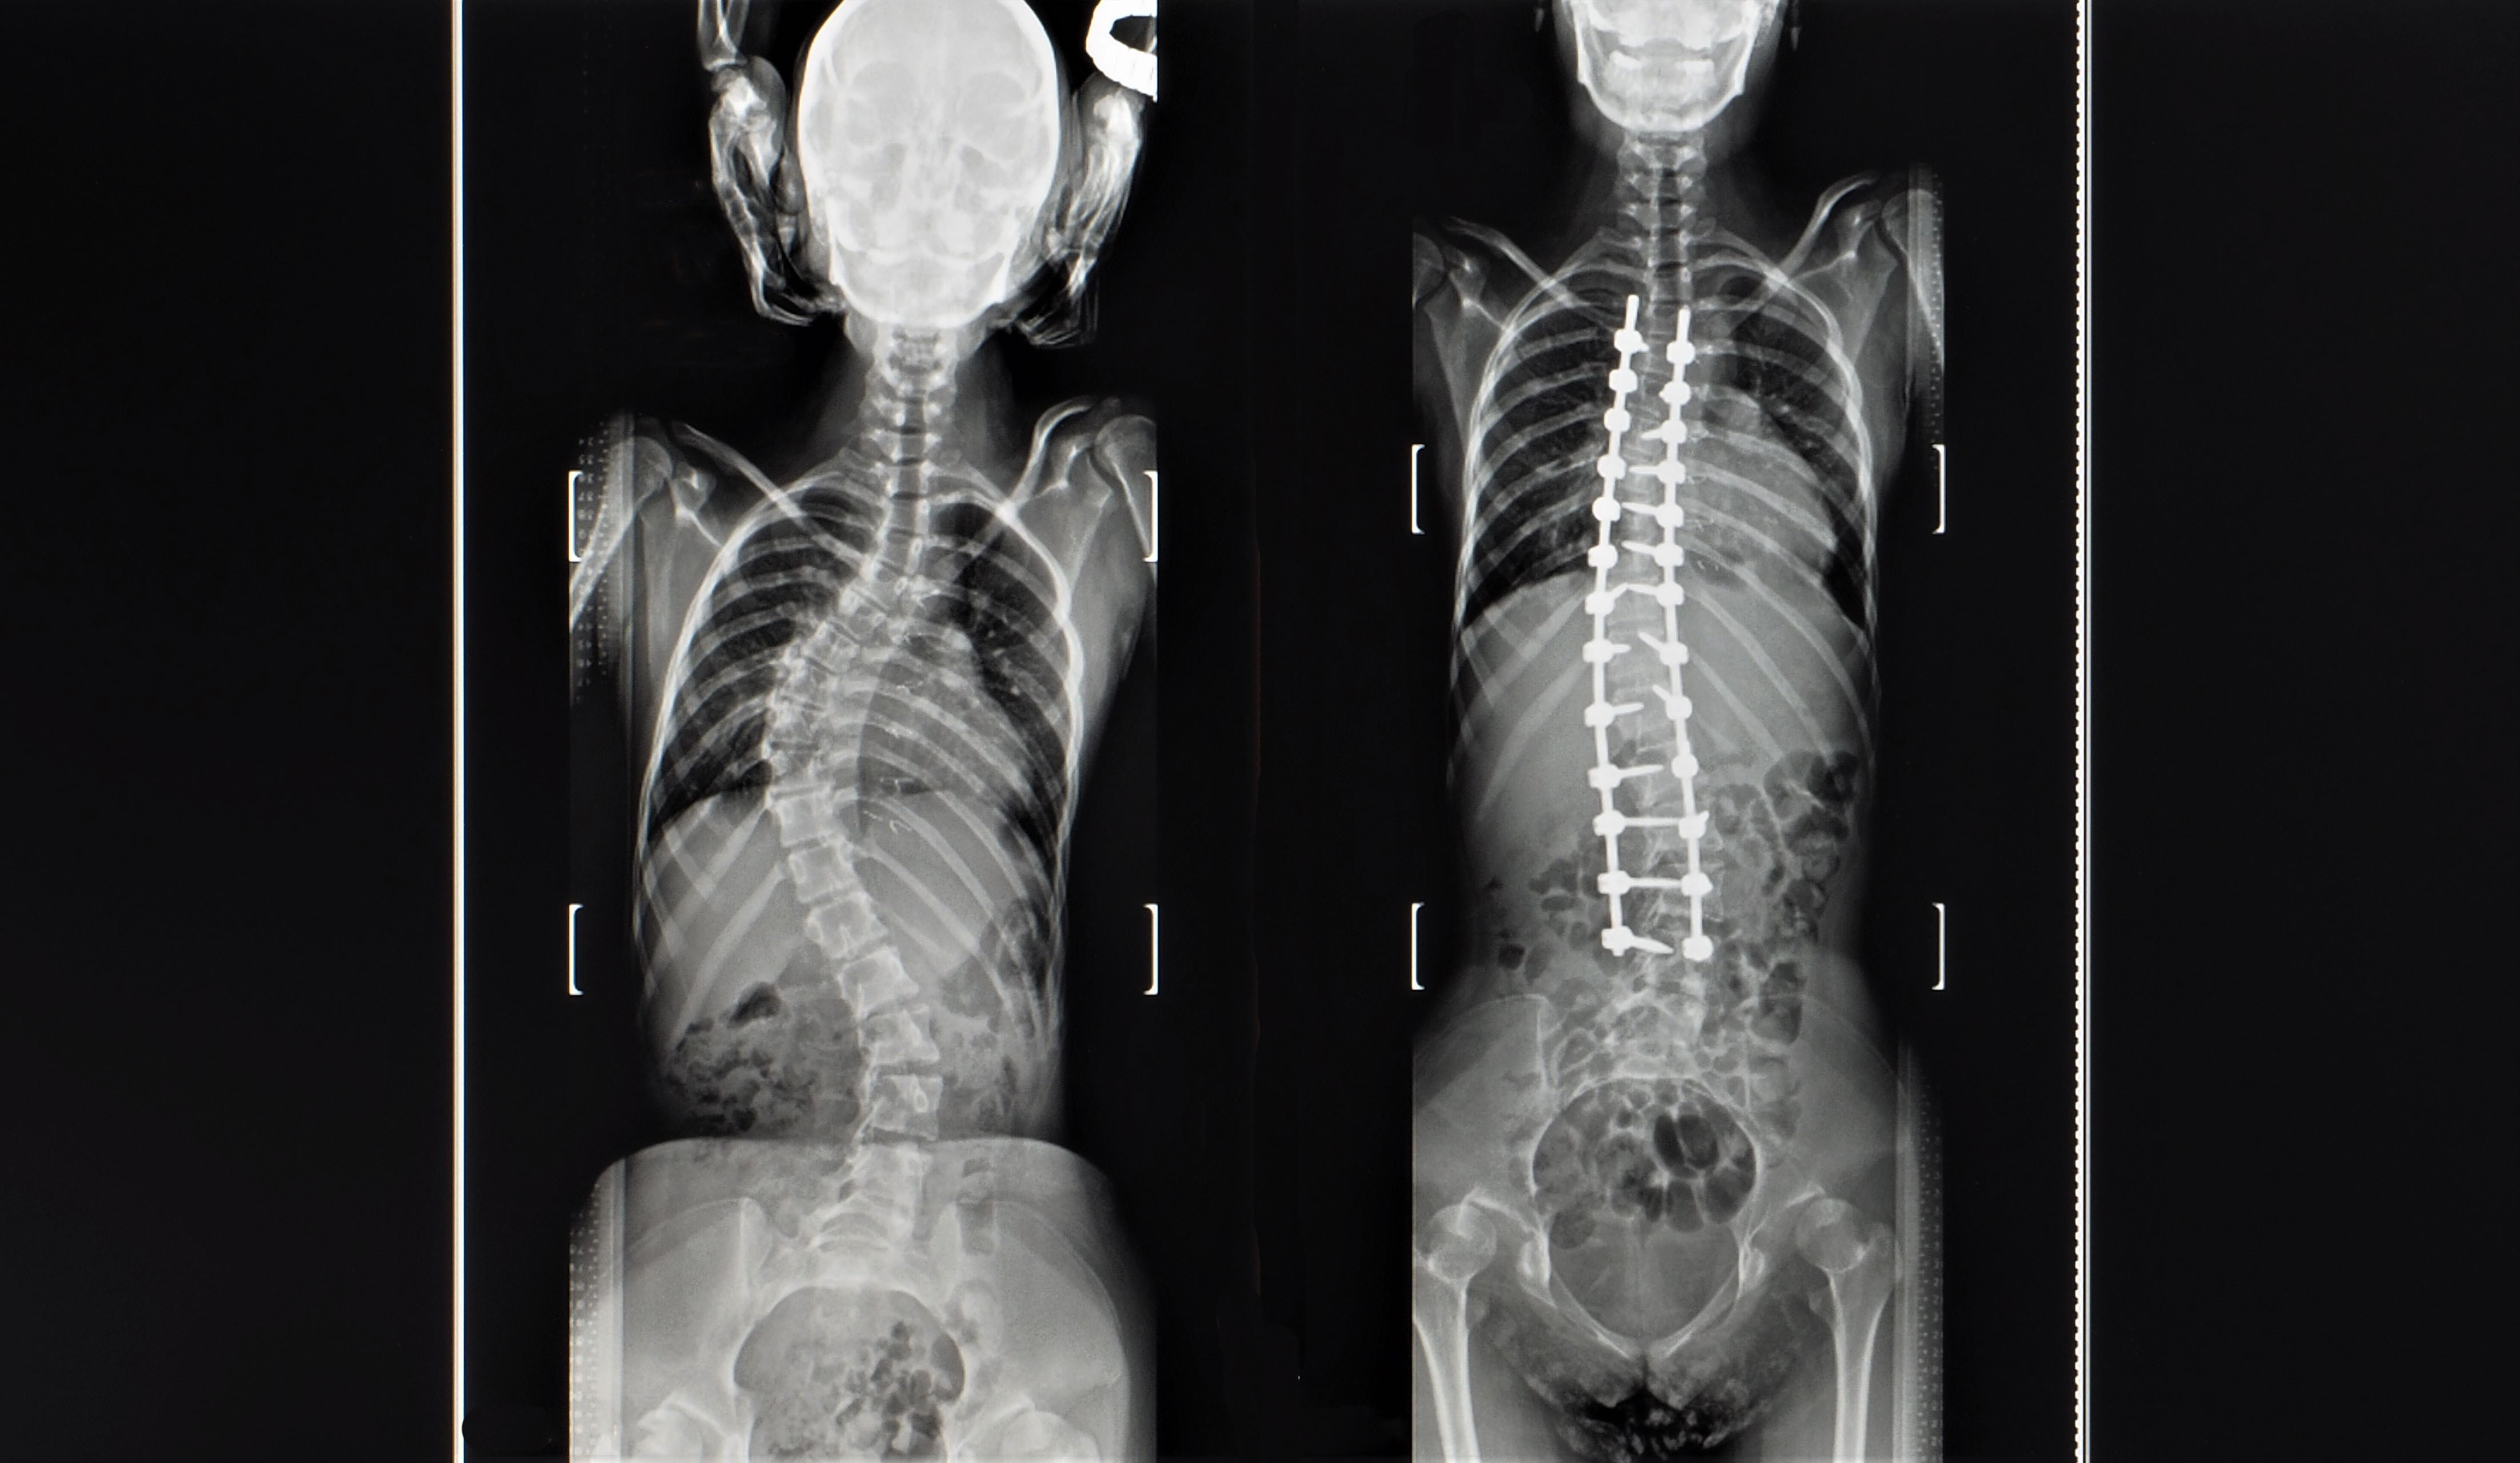

Line measurement is a subject that evaluates the misalignment of the spine and extremities through x-ray images. The line measurement evaluation method is to draw a line on the x-ray image and evaluate the alignment of the skeletal system based on the shape of the line.

More accurate diagnosis of musculoskeletal misalignment is possible through x-ray line analysis. Therefore, the treatment effect can also be expected to be maximized.

Lecture 02 - In practice, learn how to draw lines on x-ray images and evaluate them.